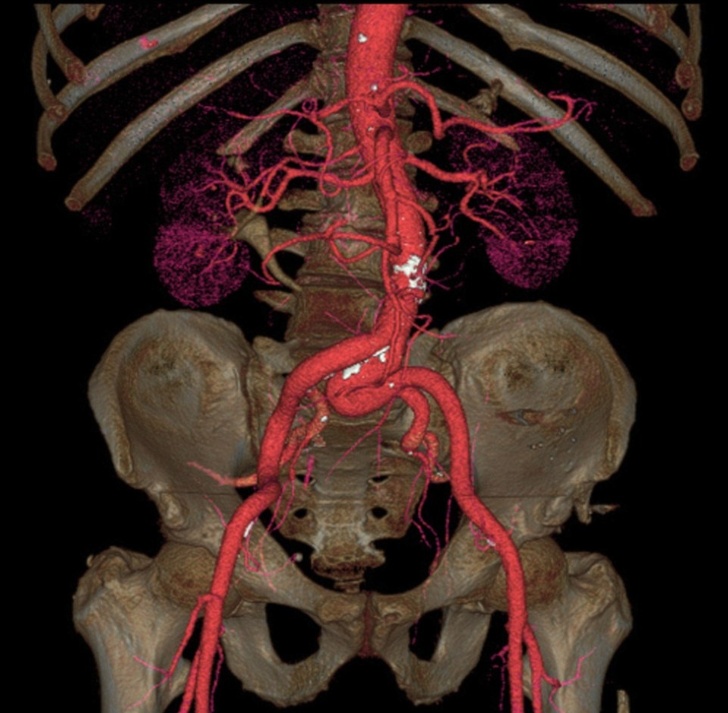

#2. The aorta is the biggest artery in our body.